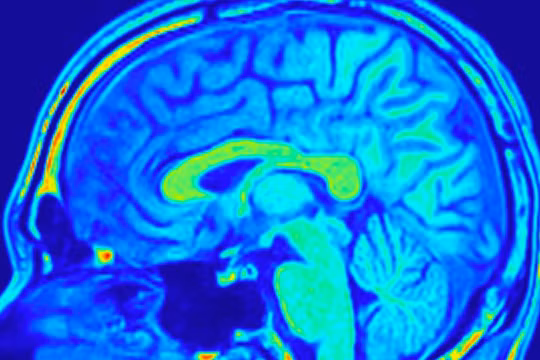

Quét não thông qua siêu máy tính có thể tăng tốc các thủ tục kiểm tra. Nguồn: iStock.

Siêu máy tính có khả năng chẩn đoán u não

Theo nhóm chuyên gia từ Đại học Texas ở Austin thì các loại u não phổ biến và nguy hiểm nhất có thể sớm được xác định nhờ sử dụng siêu máy tính. Các chuyên gia hy vọng thuật toán trong siêu máy tính sẽ giúp tăng tốc độ chẩn đoán bằng quét não